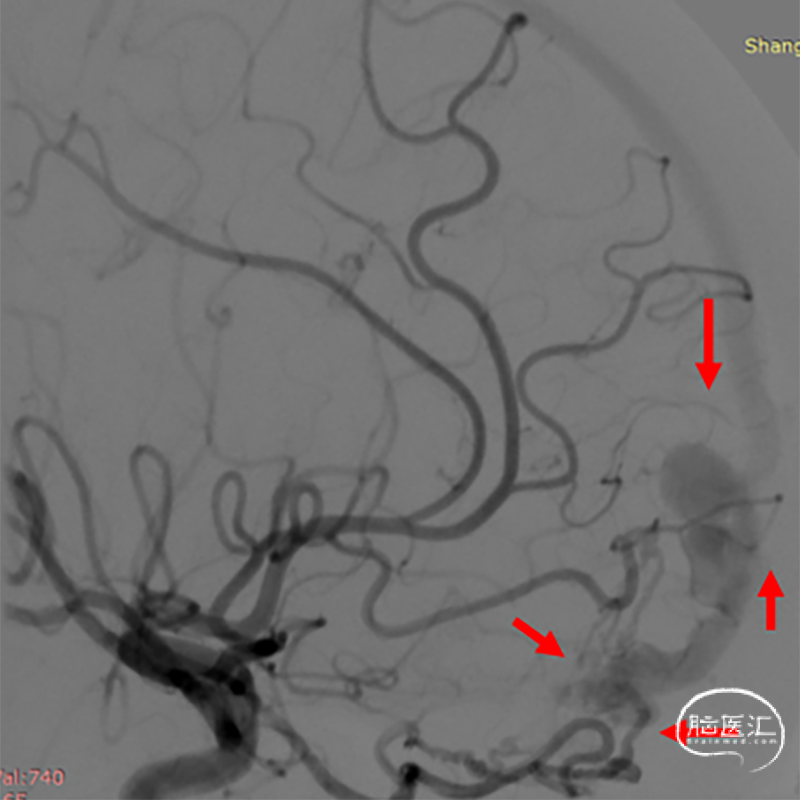

造影提示左侧前颅底眼动脉末端分支供血的DAVF经矢状窦起始段回流,回流静脉迂曲,局部可见粗大的静脉球。

局部造影显示瘘口三要素:供血动脉(红色箭头),瘘口及引流静脉(静脉球),其中蓝色箭头所示静脉期正常回流静脉。

该例患者DSA提示眼动脉分支之筛前动脉、大脑前动脉及额极动脉多支血管供血,汇集区相对分散,最终经迂曲扩张之皮层静脉汇入矢状窦。